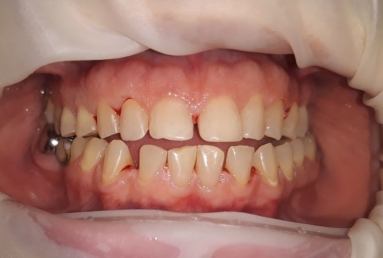

orthodontic treatment, full ceramic crowns

Our patient had general dental abrasion due to maloclusion. After orthodontic treatment, the upper teeth received full ceramic crowns, while the lower were restored with crowns and veneers.